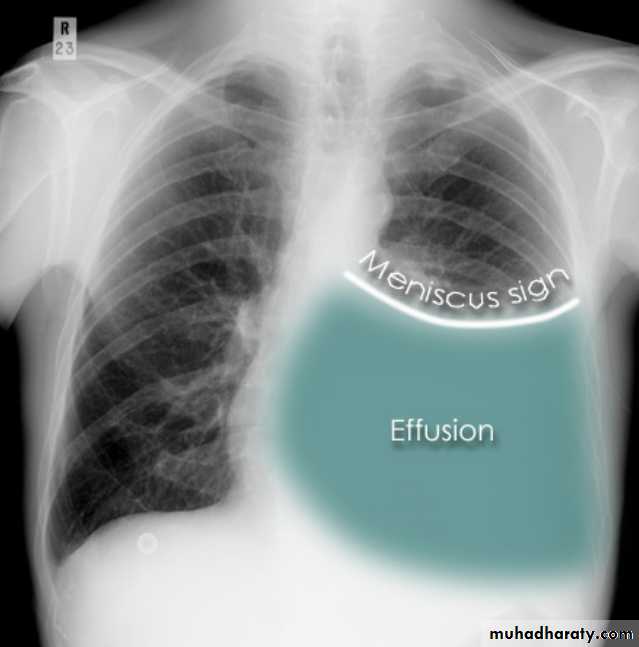

Pleural effusionPleural effusion tends to be used as a catch-all term denoting a collection of fluid within the pleural space. This can be further divided into exudates and transudates depending on the biochemical analysis of aspirated pleural fluid. Essentially it represents any pathological process which overwhelms the pleura's ability to reabsorb fluid.

Radiographic appearances

Plain radiographChest radiographs are the most commonly used examination to assess for presence of a pleural effusion, however it should be noted that on a routine erect chest x-ray as much as 250-600 ml of fluid is required before it becomes evident 6. A lateral decubitus film is most sensitive, able to identify even a small amount of fluid. At the other extreme, supine films can mask large quantities of fluid.

CXR (erect)

Both PA and AP erect films are insensitive to small amounts of fluid. Features include:

blunting of the costophrenic angle

blunting of the cardiophrenic angle

fluid within the horizontal or oblique fissures

eventually a meniscus will be seen, on frontal films seen laterally and gently sloping medially (note:

A subpulmonic effusion (infrapulmonary effusion) may be seen when there is previously established pulmonary disease, but can also be encountered in normal lungs , They are more common on the right, and usually unilateral

with large volume effusions, mediastinal shift occurs away from the effusion (note: if coexistent collapse dominates then mediastinal shift may occur towards the effusion)